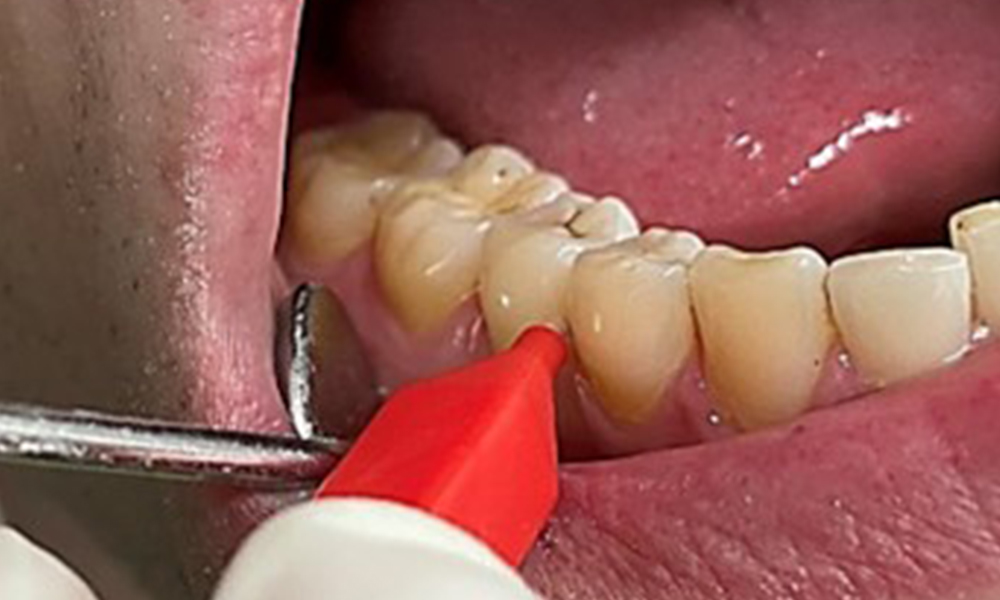

Discolouration caused by nicotine and tea consumption can be removed easily using an air polisher (Fig. 11).

Air polishing system use in the mandibular frontal lingual area (here, Proxeo Aura, W&H)

Fig. 11 Air polishing system use in the mandibular frontal lingual area (here, Proxeo Aura, W&H), © Dr R. Krapf

When using more abrasive powder, it is essential to work from a cervical to coronal direction and never point the outlet nozzle towards the gingiva to prevent potential emphysema. Good suction on the contralateral side is essential to reduce aerosol formation (Fig. 12).

Use of the air polishing system away from the sulcus with contralateral suction.

Fig. 12 Use of the air polishing system away from the sulcus with contralateral suction, © Dr R. Krapf